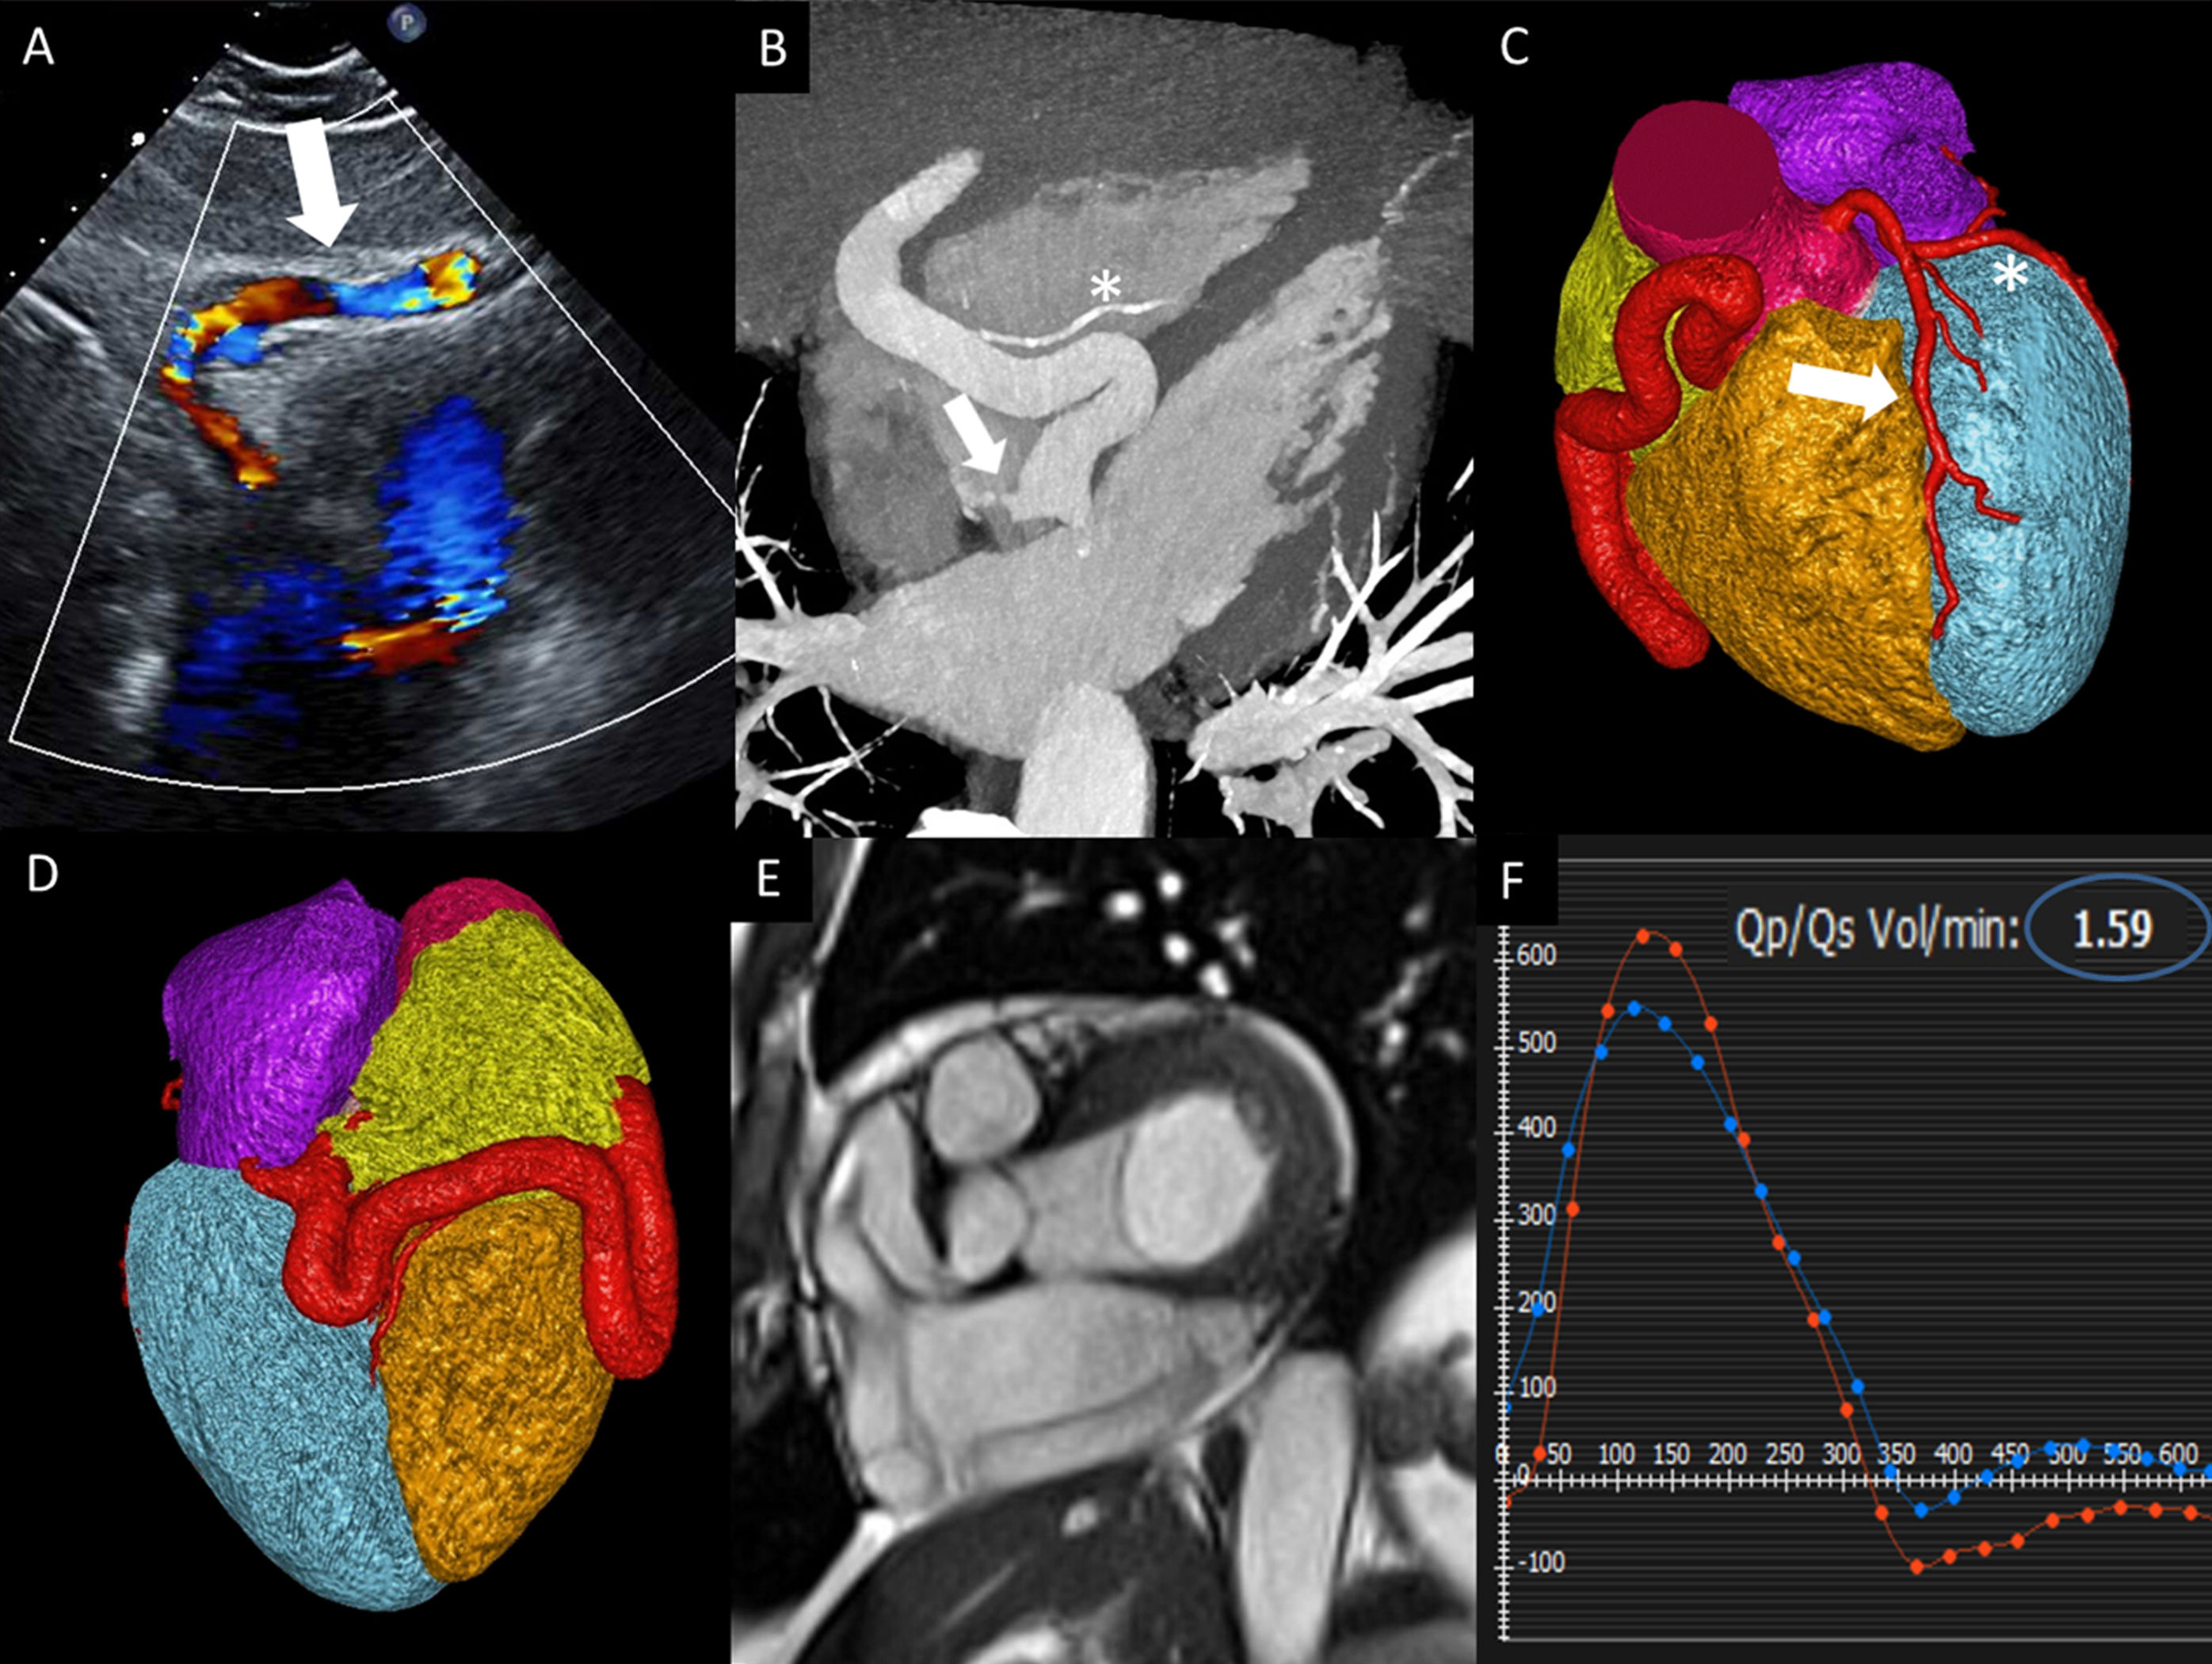

Un varón de 64 años, asintomático, acudió para una evaluación cardiovascular a causa de un soplo sistólico. En la proyección subcostal, la ecocardiografía transtorácica con Doppler mostró un flujo en una estructura tubular entre el hígado y el ventrículo derecho (figura 1A, flecha), así como un flujo anormal en el seno coronario (vídeo 1 del material adicional). Se realizó una tomografía computarizada cardiaca para completar la evaluación. La reconstrucción multiplanar, en un ángulo similar al de la ecocardiografía, mostró una arteria coronaria derecha (CD) difusamente aneurismática y tortuosa, con un diámetro de hasta 1,4cm y una conexión fistulosa con el seno coronario en la entrada de la aurícula derecha (figura 1B, flecha). La arteria descendente posterior era de tamaño normal y no presentaba signos de aneurisma (figura 1B, asterisco). Las reconstrucciones con renderización volumétrica (figura 1C,D) comparan la CD aneurismática y tortuosa con la descendente anterior izquierda (flecha, figura 1C) y la circunfleja izquierda (figura 1C, asterisco) normales. Se realizó una cardiorresonancia magnética (CRM) para evaluar la repercusión funcional de la conexión fistulosa (vídeo 2 del material adicional). En la figura 1E y el vídeo 2 del material adicional se muestran las imágenes de cine de eje corto, con los segmentos aneurismáticos proximal, medio y distal de la CD. La CRM con contraste de fase puso de manifiesto un cociente de flujo pulmonar/sistémico (Qp/Qs) de 1,6 (figura 1F, círculo azul), compatible con un cortocircuito izquierda-derecha significativo. Hasta el momento, el paciente no ha recibido ningún tratamiento y está a la espera de exploraciones de imagen de seguimiento.

Presentamos un caso muy infrecuente de fístula entre una CD aneurismática y el seno coronario, con una evaluación multimodal que integra la anatomía compleja y la función.